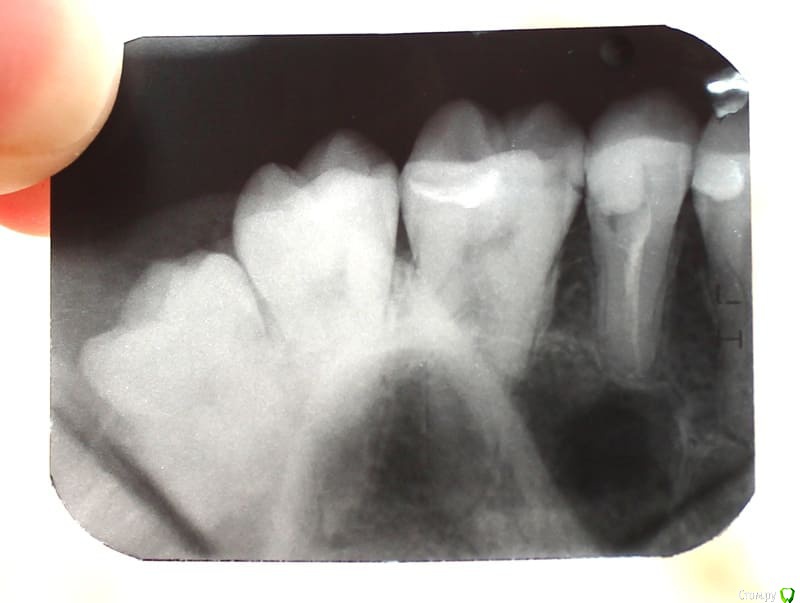

annie23 Опубликовано 11 июня, 2018 Поделиться Опубликовано 11 июня, 2018 Добрый день! Нужна ваша консультация. В январе этого года пролечила пульпит 15 зуба. В какой-то момент он начал реагировать на холодное/горячее, сейчас такого не наблюдается. Изредка где-то далеко чувствую тянущую боль (но это скорее я придираюсь). Что беспокоит на данный момент: 1. Кажется, что внутри забыли что-то инородное (как будто много пломбировочного материала наложили). Один из стоматологов чуть-чуть прошлифовал пломбу, но это ощущение все равно сохраняется.2. Запах от зуба. Он, простите, зловонный (точно такой же как до лечения), особенно это ощущается после чистки зубной нитью. Снимков до пломбировки канала нет, лечила в государственной. После была у двух частных стоматологов, оба развели руками и сказали, что все нормально. Скажите, с этим нужно научиться жить или с этим можно что-то сделать?! (И еще у меня были подозрения на кисту, но никто об этом не упомянул) Ссылка на комментарий

red_butler Опубликовано 11 июня, 2018 Поделиться Опубликовано 11 июня, 2018 Пятый, перелечить корневые каналы и протезировать искусственной коронкой, на шестом лечить кариес на боковой поверхности. 1 1 Ссылка на комментарий

St. Опубликовано 11 июня, 2018 Поделиться Опубликовано 11 июня, 2018 По снимку от зуба осталось не так много и есть большой риск сломать его в будущем. Коронка защитит от этого Ссылка на комментарий